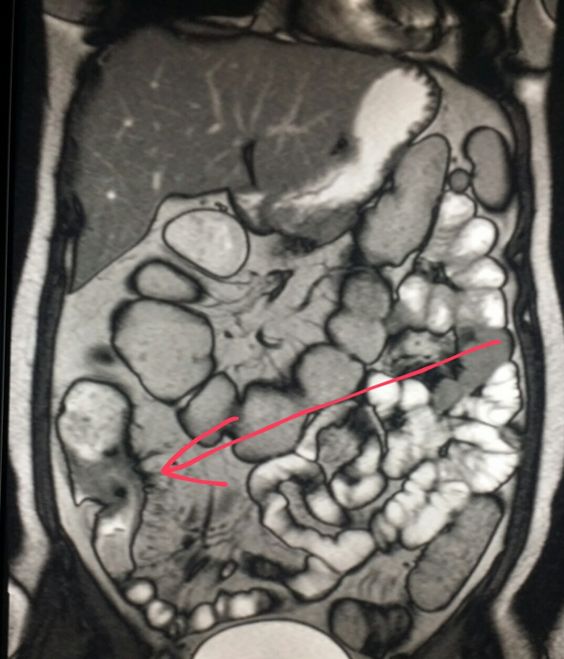

Метод гидро МРТ — это введение двойного контраста (одновременное оральное и внутривенное введение контрастирующего препарата для улучшения качества изображения проблемной области) в органы желудочно-кишечного тракта (ЖКТ). Этот метод, как показывает статистика, увеличивает возможность обнаружения различных воспалений, опухолей, полипов, кровотечений на самых ранних стадиях.

Для получения хороших снимков толстой кишки проводят гидро-МРТ. Основными аспектами метода является двойное контрастирование. Пациент перед обследованием принимает до полутора литров воды (которые естественным путём перемещается в кишечник), и дополнительно внутривенно водится контраст, накапливающийся в стенках кишечника. Вседствии проведённых манипуляций толстая и тонкая кишка в достаточной мере растягиваются. Гидро МРТ в полной мере покажет наличие воспалённого участка тонкой кишки, обозначит протяжённость патологии и возможные вторичные проявления заболеваний (метастазы). Пациент размещается на столе аппарата МРТ животом вниз. Процедура длиться около часа. После обследования вы получите расшифровки, которые помогут поставить верный диагноз.

Когда мы слышим слово "гидро", то понимаем, что метод основан на применении воды. Действительно, гидро МРТ — это доскональное обследование при помощи большого количества воды с добавлением препаратов, замедляющих всасывание. Обязательным условием для проведения МРТ является хорошее растяжение кишечника. Достигнуть такого результата можно при помощи наполнения его жидкостью. Основные показания к проведению обследования — это наличие воспалительных процессов.

К таковым относятся язвенный колит, болезнь Крона, опухоли (злокачественные и доброкачественные), врождённая патология кишечника. МРТ назначают тогда, когда пациент уже сдал анализы, и у врачей появились сомнения для постановки точного диагноза. При помощи гидро МРТ можно выявить воспалённый участок тонкого кишечника, установить размеры поражённой области. Помимо этого при обследовании выявляются метастазы (вторичные новообразования) в отдалённых соседних органах, что даёт полноценную картину состояния организма человека.

На консультациях пациенты часто задают вопрос, а что означает контрастирование, и делают ли с контрастом данное обследование? Да, гидро МРТ основано на двойном контрастировании стенок кишечника. Пациент выпивает раствор на основе воды (естественный контраст). Дополнительно вводят внутривенно препарат, который обеспечивает на изображениях подсветку стенок кишечника. Контрастный препарат не содержит йод (как, например, при компьютерной томографии), поэтому в очень редких случаях может вызвать аллергию у человека.